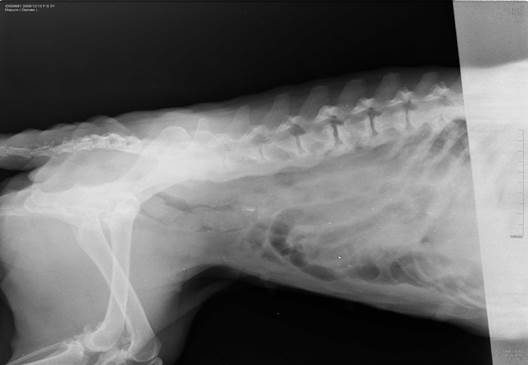

Диагноз дискоспондилита собак основывается на характерный рентгенологических изменениях совместно с подходящей историей болезни и данных обследования.

Радиографическое исследование при дискоспондилите выявляет коллапс межпозвоночного пространства в зоне поражения, лизис концевых пластинок позвонков и различные компоненты пролиферации и склероза концевых пластинок. Поражения при дискоспондилите собак могут быть как единичными так и множественными, чаще всего инфекционный процесс развивается в пояснично-крестцовом соединении (L7-S1), затем по частоте встречаемости поражений идут диски грудопоясничного отдела, и реже всего дискоспондилит развивается в шейных отделах позвоночника.

Радиографические изменения на начальных стадиях дискоспондилита обнаруживаются не всегда, они могут запаздывать на 2-4 недели. У пациентов с признаками дискоспондилита, но без характерных рентгенологических изменений – болезнь все же может присутствовать, в таких случаях, более ценным методом диагностики может служить компьютерная и магниторезонансная томография.